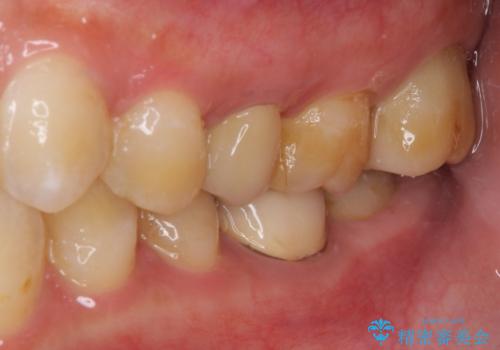

来院されたときには、神経を全て取り除くことになるであろうと思っていらっしゃいましたが、結果としては歯根部分の歯髄を残すことができました。

神経組織を全部または部分的に除去することが分かっていたため、ラバーダムなどの環境を整え、無菌的環境下にて処置を進めて行きました。

虫歯は深くまで進行しており、歯冠部の神経から出血が認められました。神経を部分的に除去したところ出血が治まったので、生体親和性の非常に高いセメントにて充填し、仮封をしました。

後日状態を確認したところ、残された神経に異常は認められませんでした。

欠損歯質は比較的小さかったため、セラミックインレーにて修復治療を行いました。